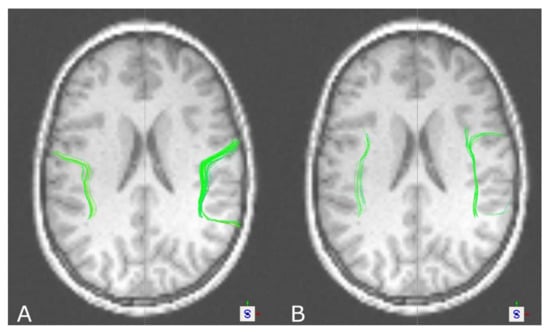

3.3. The Arcuate Fascicle

3.2. The Optic Radiation